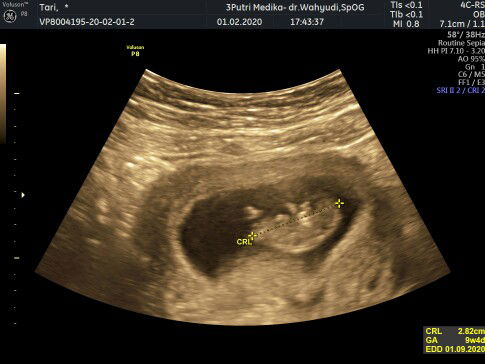

hasil usg selisih 2w dg HPHT

menurut HPHT harusnya sudah jalan 12w. tp setelah USG baru jalan 10w. anda yg sama gk bunda? udah semangatnya mau lewatin TM 1 ternyata hitungan usg mundur ?